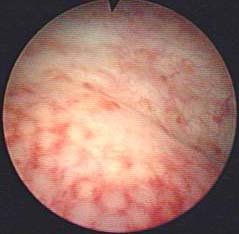

腺性膀胱炎的概述 腺性膀胱炎是膀胱粘膜移行上皮由于各种原因转化为腺上皮的转化性病变。其临床表现无特征性。 腺性膀胱炎医院推荐 1条患者评价 2条患者评价 1条患者

腺性膀胱炎--腺样结构(图)(腺性膀胱炎|粘膜下层